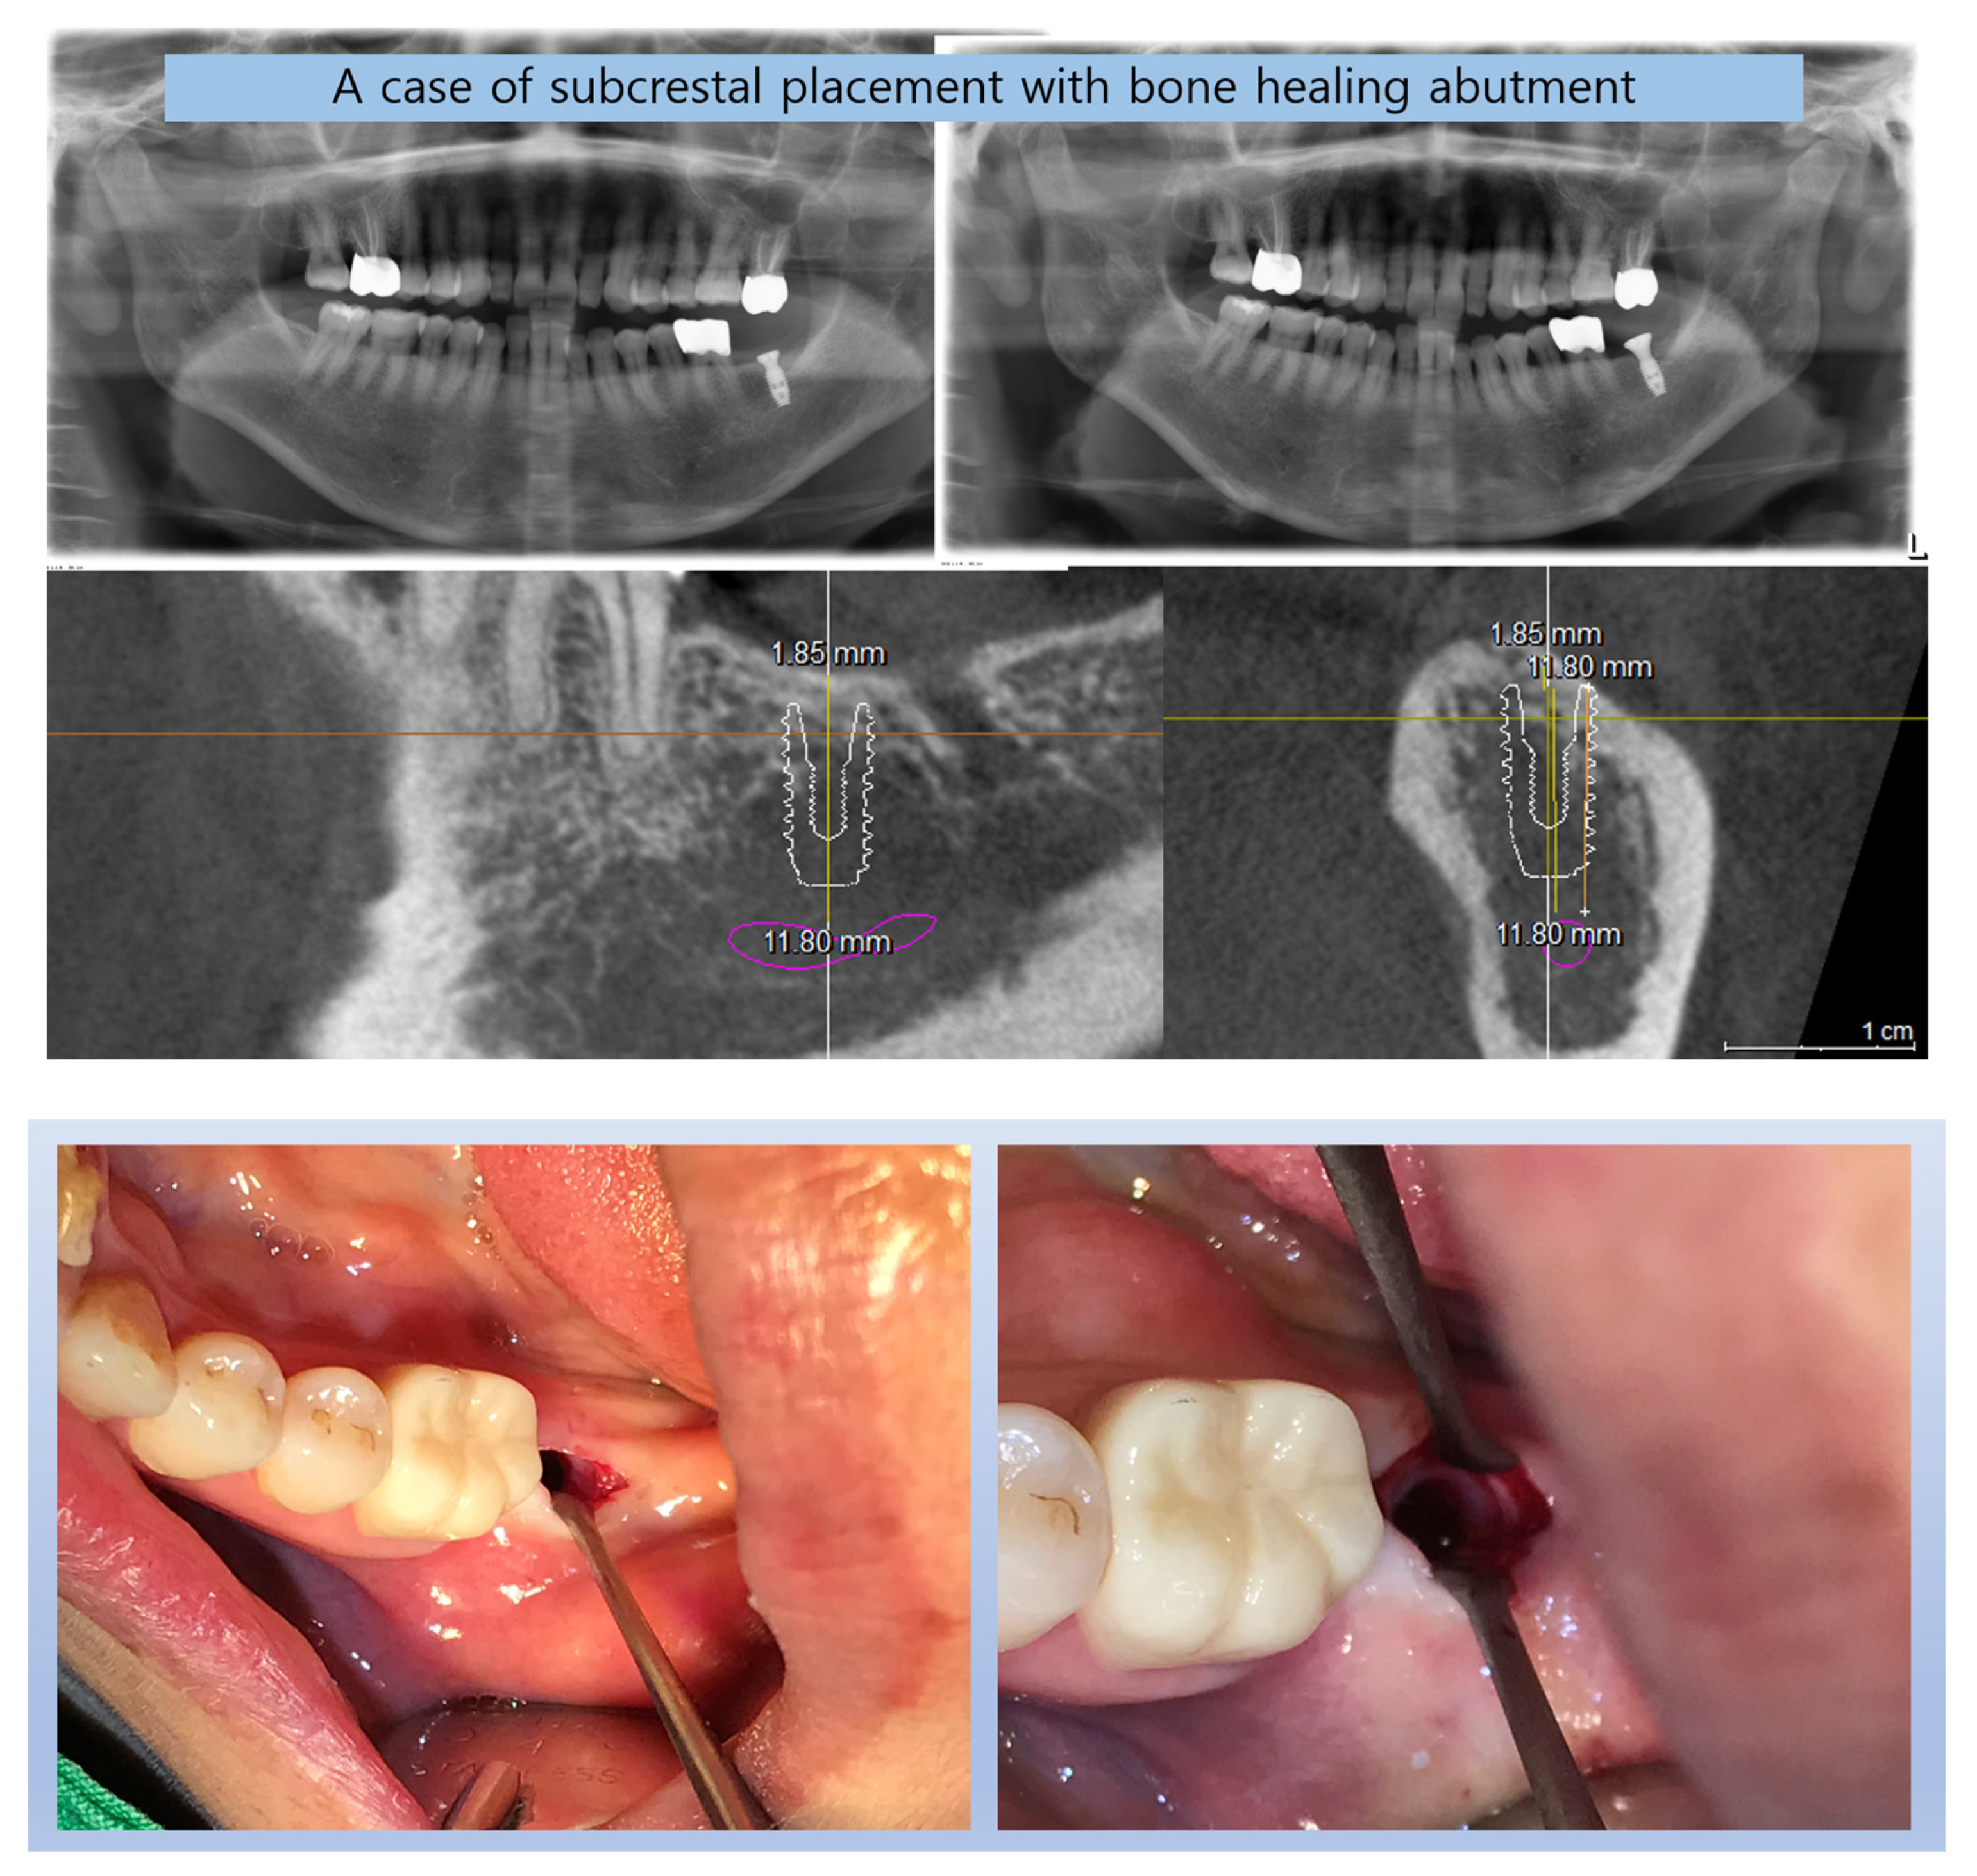

Figure 8. Subcrestal Placement of Fixtures and Healing Abutments. This image illustrates the subcrestal placement of fixtures, with healing abutments measuring 5 mm in diameter and 2.5 mm in height connected. The flap was then sutured to achieve primary closure, ensuring secure and proper healing conditions.

Preprints 103958 g008

Secondary Operations for Prosthetic Procedures (after 3 months):

• Uncovering and Abutment Connection: The second surgical operations involved uncovering the sites and connecting longer healing abutments that matched the profile of the initially embedded healing abutments.

• Impression and Prosthesis Fabrication: Using the impression coping technique, final implant crowns were fabricated. These crowns were designed with predetermined ready-made abutments from stock, maintaining the same size as the healing abutments (5 mm diameter and 2.5 mm gingival cuff). This sizing helps to avoid bony interference during the fitting of implant abutment prostheses.

• Crown Design: The clinical crowns were shaped with a gradual emerging angle from the abutment margin toward the cervical part of the neighboring natural teeth, effectively emulating a natural tooth shape. This design is enabled by the ample vertical distance afforded by subcrestal placement, which facilitates a smooth and gradual emergent profile.